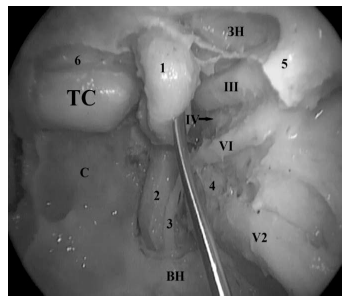

Кавернозный синус содержит кавернозный сегмент ВСА, окруженный волокнами симпатического сплетения, отводящий нерв (VI) и систему венозных полостей различного строения. В латеральной стенке кавернозного синуса проходят глазодвигательный нерв (III), блоковый нерв (IV) и первая ветвь тройничного нерва — глазной нерв (V1). Верхнечелюстной (V2) и нижнечелюстной (V3) нервы проходят между двумя листками ТМО латеральнее и ниже кавернозного синуса (рис. 2).

Рис. 2. Латероселлярное пространство — анатомический препарат (0º эндоскоп). Кавернозный сегмент ВСА (1) смещен медиально. Визуализируется латеральная стенка КС с проходящими в ней черепно-мозговыми нервами: 1 — кавернозный сегмент ВСА; 2 — паракливальный отдел ВСА; 3 — симпатическое сплетение ВСА; 4 — ганглий тройничного нерва; 5 — верхняя глазничная щель; 6 — межкавернозный синус; ТС — гипофиз; ЗН — зрительный нерв; ВН — крыловидный (видиев) нерв; III — глазодвигательный нерв; IV — блоковый нерв; VI — отводящий нерв, за которым располагается первая ветвь тройничного нерва; V2 — вторая ветвь тройничного нерва (верхнечелюстной нерв)